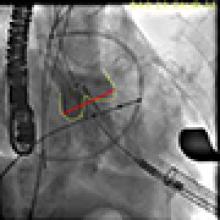

- The valve is deployed in position during direct fluoroscopic visualization (Figure 6) with another brief period of rapid ventricular pacing to reduce ejection. Respirations are also suspended during this period to limit the movement within the thoracic cavity and optimize visualization. Clear communication is critical during this brief period of the procedure and so one person commands the timing of each step of the procedure in a standard clear format.

[8]Figure 6. The valve is deployed in position during direct fluoroscopic visualization with a brief period of rapid ventricular pacing to reduce ejection.